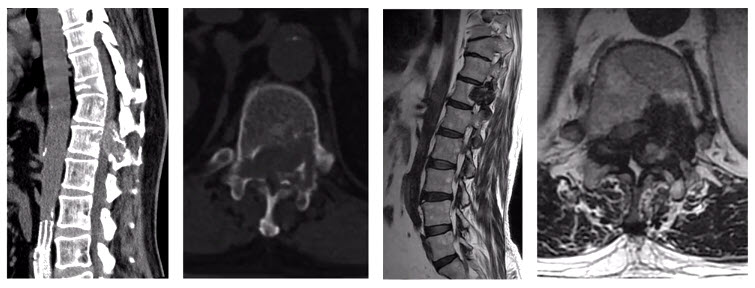

This time, after the tumor arteries embolization, a more aggressive tumor excision was undertaken with sacrificing the nerve roots. The postoperative pathology showed the tumor composed of abundant epithelioid osteoblasts, but no signs of malignant appearance. The postoperative CT and MRI showed the recurrent tumor was excised grossly.

Let’s consider another case. It was a 55-year-old male presenting with incomplete paralyzed, Frankel C. Osteoblastoma of T12 was diagnosed by biopsy. It was Enneking stage 3 lesion. We did an intentional intralesional en bloc spondylectomy, then radiotherapy after the surgery. There was no recurrence in the two-year follow-up.

But sometimes things are more complicated. Another case involved a 33-year-old female. The chest X-ray examination found an osteogenic spinal lesion. The CT scan showed osteolytic lesions of T9 left vertebral body, facet joints and rib, with extensive reactive bone formation.

There was obvious spinal cord compression, and the PET/CT revealed extensive uptake.

We did a CT-guided biopsy. Although we consulted the result in three hospitals, the pathologists failed to give us a definite diagnosis, whether it was osteoblastoma or a low-grade osteosarcoma.

So, we treated it as if it was malignant. We did an anterior-posterior approach sagittal en bloc resection of the T8 to T10. In the anterior approach, we dissected the tumor. In posterior approach, we transected the body with an ultrasonic cutter. We resected three segments en bloc. The margin was sufficient, not only pathologically, but also by CT scan.

The postoperative pathological diagnosis is still unclear. The pathologists gave us four diagnoses: osteoblastoma, epithelioid osteoblastoma, low-grade osteosarcoma, or even osteomyelitis.

Nevertheless, the patient was doing well in the 2-year follow-up. There is no recurrence.

In another case, an 11 years-old girl was diagnosed with L5 osteoblastoma by CT guided biopsy. Because the tumor invaded the whole L5 vertebral body and the right facet joint and invaded posterior cortex into epidural space forming a soft tissue, it was diagnosed as Enneking S3.

The en bloc spondylectomy was undertaken by posterior approach. Postoperative gross specimen and pathological examination showed negative margin. The tumor showed no recurrence in the 2.5-year-follow-up.